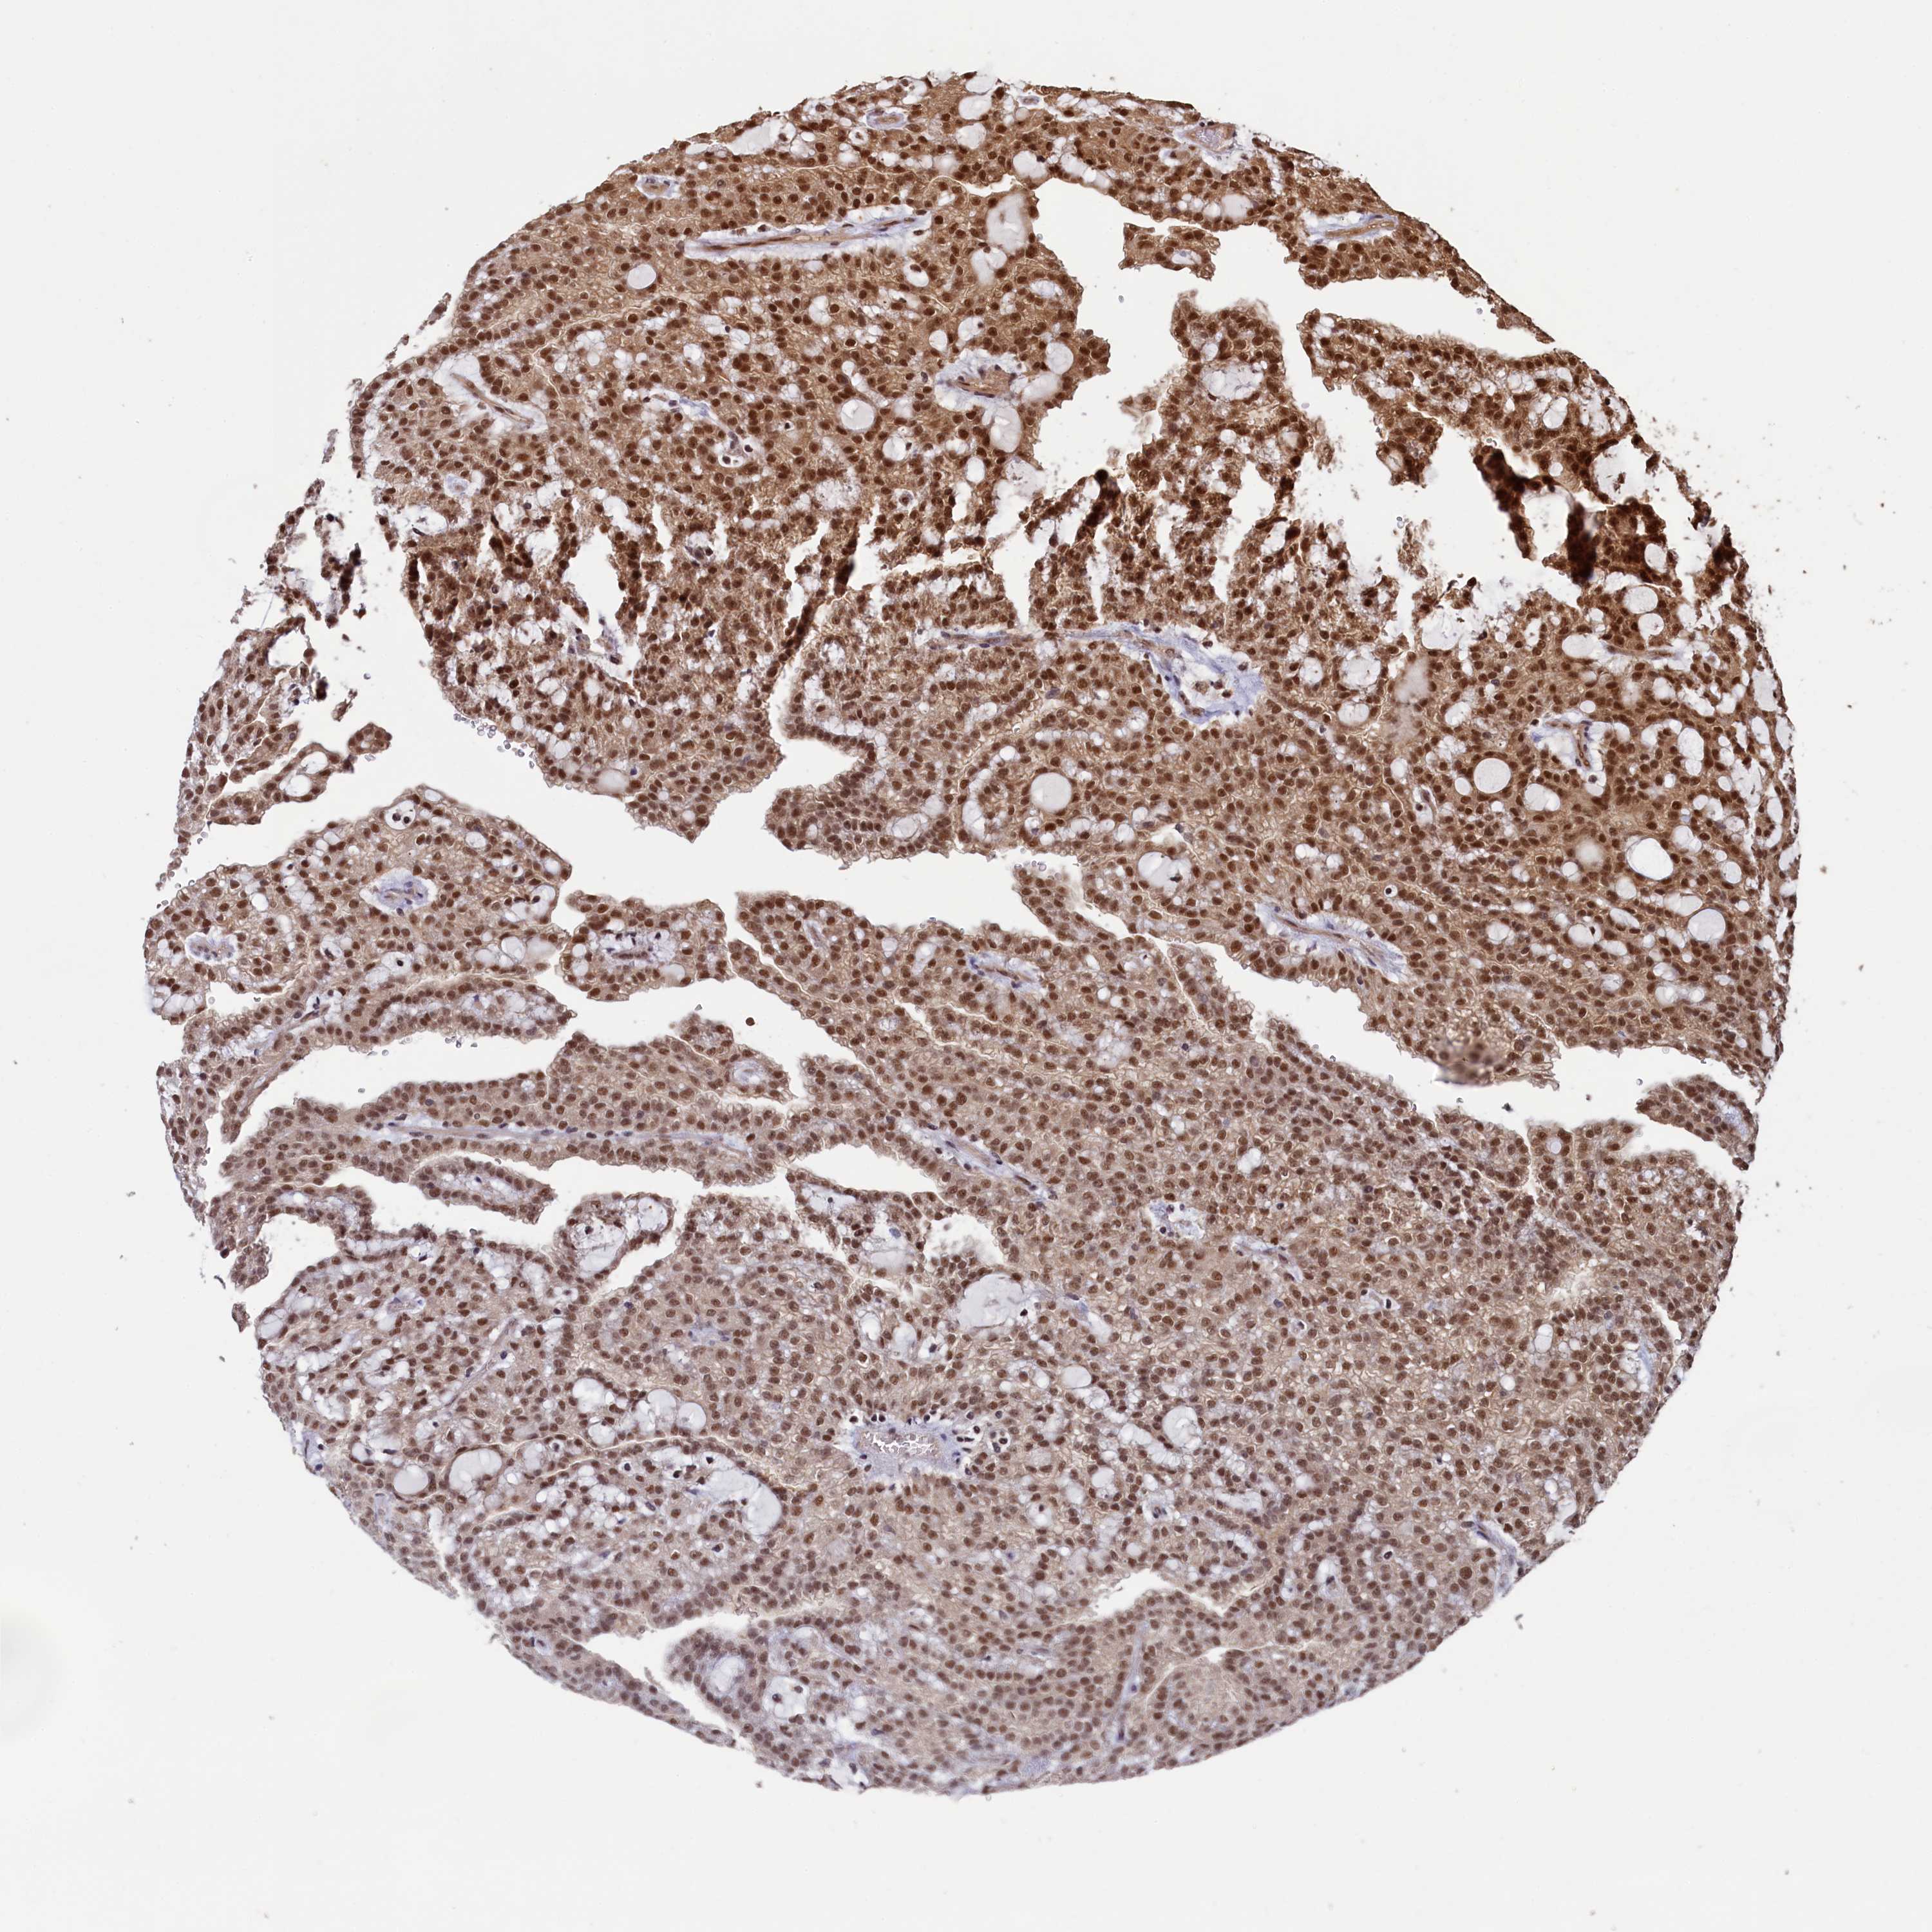

KIDNEY RENAL CLEAR CELL CARCINOMA (VALIDATION) - Interactive survival scatter ploti

The Survival Scatter plot shows the clinical status (i.e. dead or alive) for all individuals in the patient cohort, based on the same data that underlies the corresponding Kaplan-Meier plots. Patients that are alive at last time for follow-up are shown in blue and patients who have died during the study are shown in red.

The x-axis shows the expression levels (FPKM) of the investigated gene in the tumor tissue at the time of diagnosis. The y-axis shows the follow-up time after diagnosis (years). Both axes are complimented with kernel density curves demonstrating the data density over the axes. The top density plot shows the expression levels (FPKM) distribution among dead (red) and alive patients (blue). The right density plot shows the data density of the survived years of dead patients with high and low expression levels respectively, stratified using the cutoff indicated by the vertical dashed line through the Survival Scatter plot. This cutoff is automatically defined based on the FPKM cutoff that minimizes the p-score. The cutoff can be changed by dragging the vertical line or by entering a cutoff value in the square labeled "Current cut-off".

Under the Survival Scatter plot the p-score landscape (black curve; left axis) is shown together with dead median separation (red curve; right axis). Dead median separation is the difference in median mRNA expression between patients who have died with high and low expression, respectively. It is calculated as follows: median FPKM expression of dead patients with high expression - median FPKM expression of dead patients with low expression. This is intended to aid the user in visually exploring custom cutoffs and the associated p-scores and dead median separation.

& Survival analysisi

Kaplan-Meier plots summarize results from analysis of correlation between mRNA expression level and patient survival. Patients were divided based on level of expression into one of the two groups "low" (under cut off) or "high" (over cut off). X-axis shows time for survival (years) and y-axis shows the probability of survival, where 1.0 corresponds to 100 percent.

NAE1 is not prognostic in Kidney Renal Clear Cell Carcinoma (validation)

: 28.09

Average pTPM 36.0

Number of samples 100